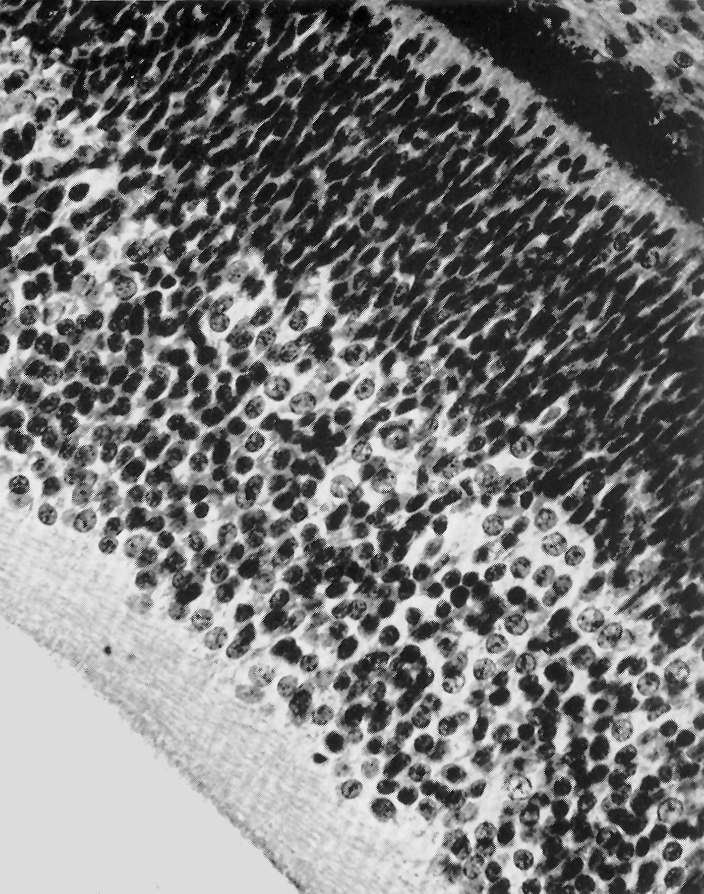

Retina. Internal to the pigmented stratum, the following layers can be seen: proliferative zone and external neuroblastic layer, internal neuroblastic layer, nerve fiber layer, and internal limiting membrane.

O'Rahilly, 1966 Fig. 53

Keywords: external neuroblastic layer of retina, internal limiting membrane of retina, internal neuroblastic layer of retina, nerve fiber layer of retina, pigmented stratum of retina, proliferative zone of retina, retina